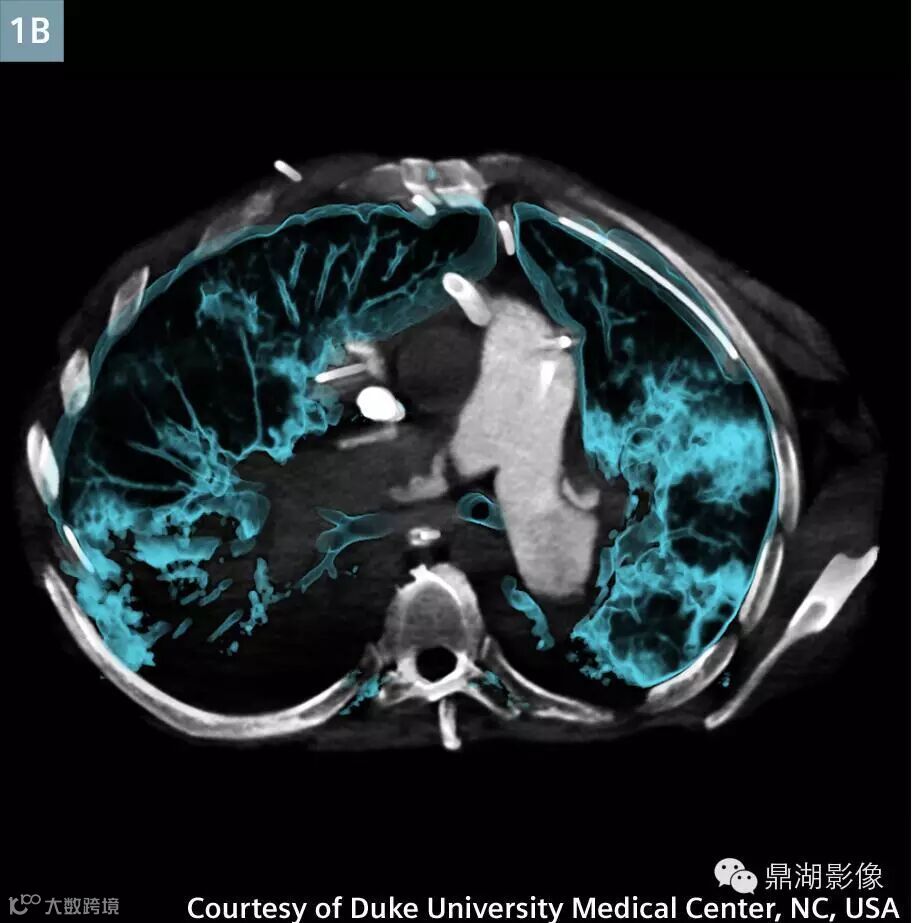

Axial contrast-enhanced (Fig. 1A) and VRT (Fig. 1B) image at the level of the main pulmonary artery: There are irregular filling defects (arrow) in the occluded right main pulmonary artery consistent with thrombosis.

肺动脉CTA显示新的多发性肺栓塞和右动脉完全闭塞(图1)。左下叶肺动脉和静脉灌注一直持续(图3)。存在广泛右肺动脉梗塞(图2)。上腔静脉,右心房,右心室充满造影剂,造影剂回流进入肝静脉和下腔静脉(图5A)。主肺动脉CT值衰减大于250亨氏单位,这可以让医生确定扫描的诊断质量。ECMO系统和主动脉的分支未显影,体现了良好的团注时间(图4)。